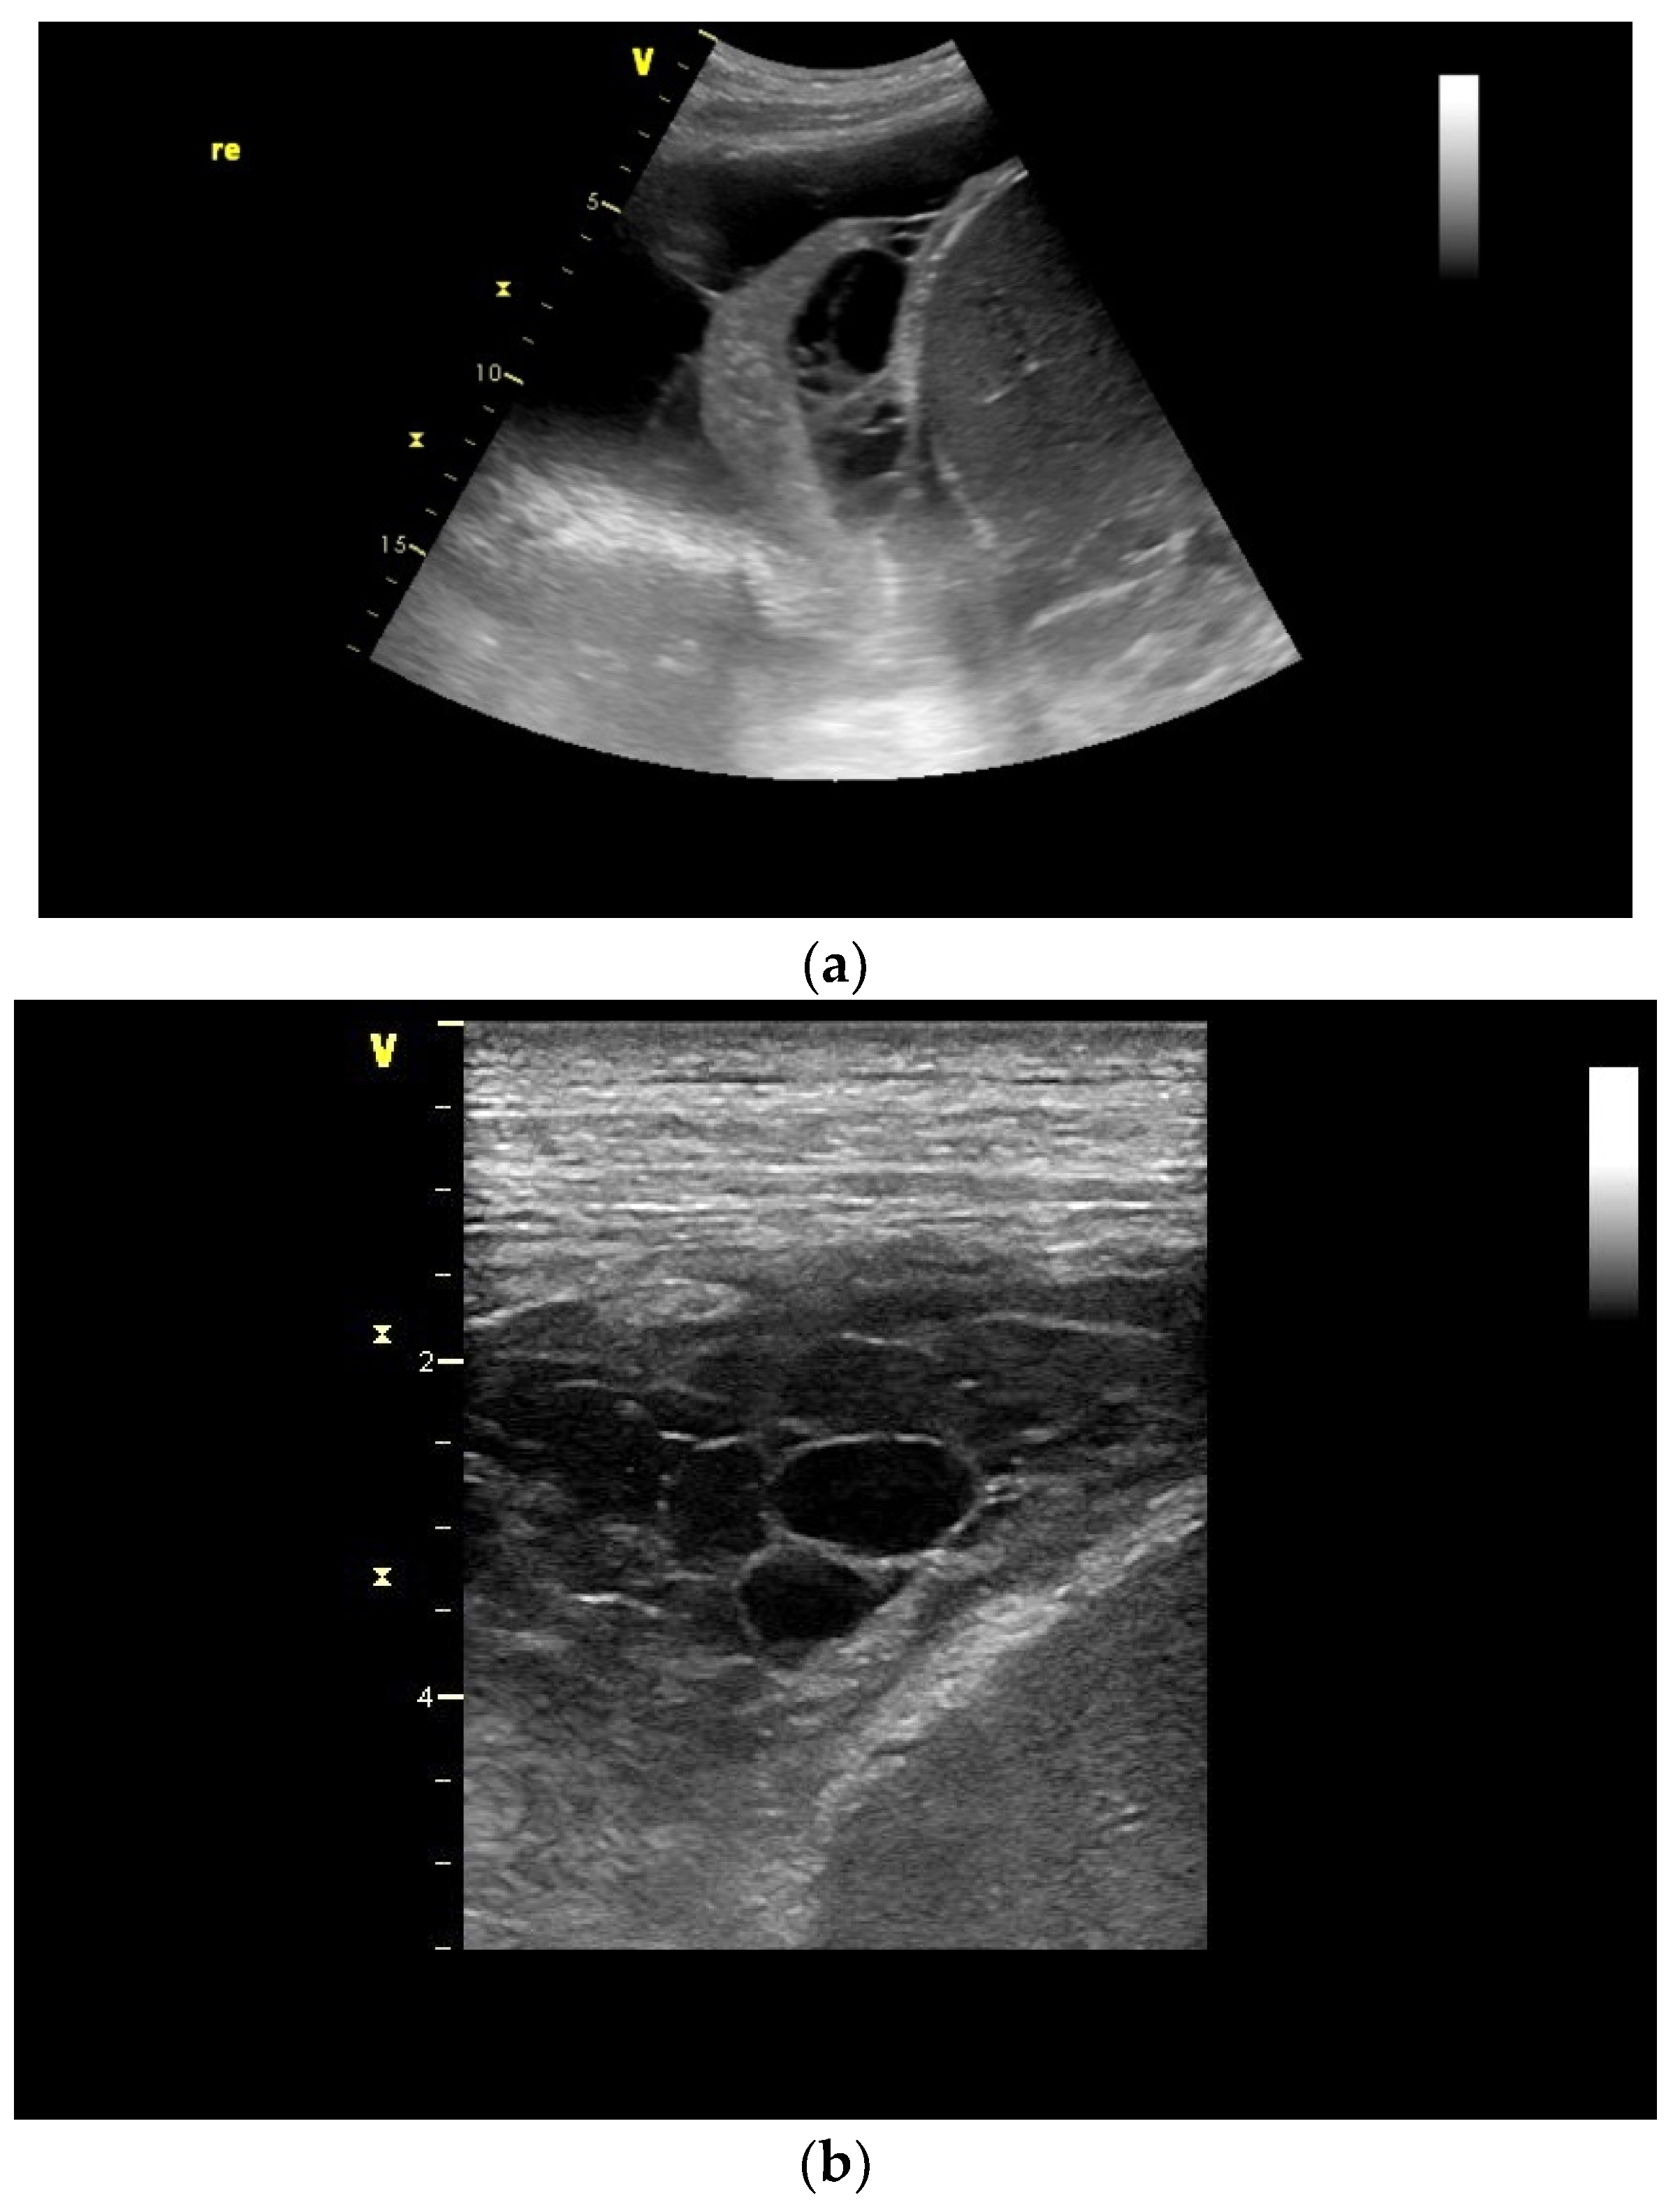

| Schwannoma | Round or oval, smoothly bordered, hypoechoic. Cystic parts are typical, especially in larger tumors. In CEUS, the solid parts are hyper-enhanced. |